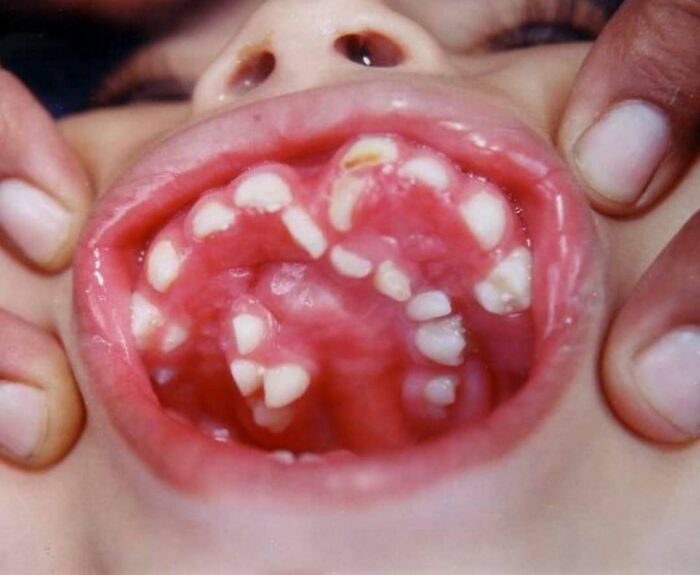

#4 Zriedkavý prípad dieťaťa trpiaceho stavom nazývaným hyperdontia